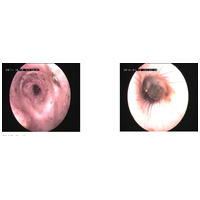

Állatorvosi vélemény: a külső hallójárat-gyulladás kezelése mindig helyi ápolást igényel. A Dermoscent PYOclean Oto természetes, cerumenolitikus (fülzsíroldó), tisztító és biofilm-ellenes tulajdonságai révén ideális megoldás a gyulladásos fülek ápolására, illetve a visszatérő otitisek megelőzésére. Klinikai vizsgálatok igazolták, hogy rendszeres használata:

- +43%-kal hatékonyabbá teszi a fülzsír eltávolítását,

- -91%-kal csökkenti a bőrpírt,

- -75%-kal mérsékli a viszketést.

Egy francia állatorvosi tanulmányban több olyan kutyán is alkalmazták, amelyeknél a fülproblémák a nem megfelelő higiénia miatt tértek vissza. A PYOclean Oto rendszeres használatával jelentősen csökkent az állatorvosi konzultációk száma.